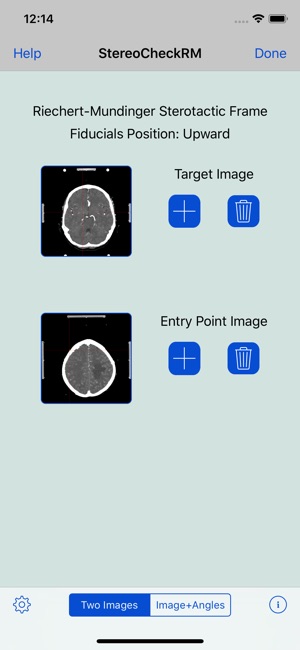

StereoCheckRM is a mobile application designed to compute target parameters of the Riechert-Mundinger stereotactic apparatus. It is intended to be a second-check tool.

Two methods are available:

- Using two CT or MR images corresponding to the target point, which will be reached by the probe, and the trepanation point where the probe will enter the skull.

- Using one CT or MR image corresponding to the target point, and entering the value of SW and HW angles directly.

2. Select method of calculation to be used: Two Images or Image + Angles.

3. Tap the + button of the Target Image to select the image from the camera roll.

4. If "Two images"method was selected, tap the + button of Entry Point Image to select the image from the camera roll. If Image + Angles was selected, enter the values of SW and HW angles.